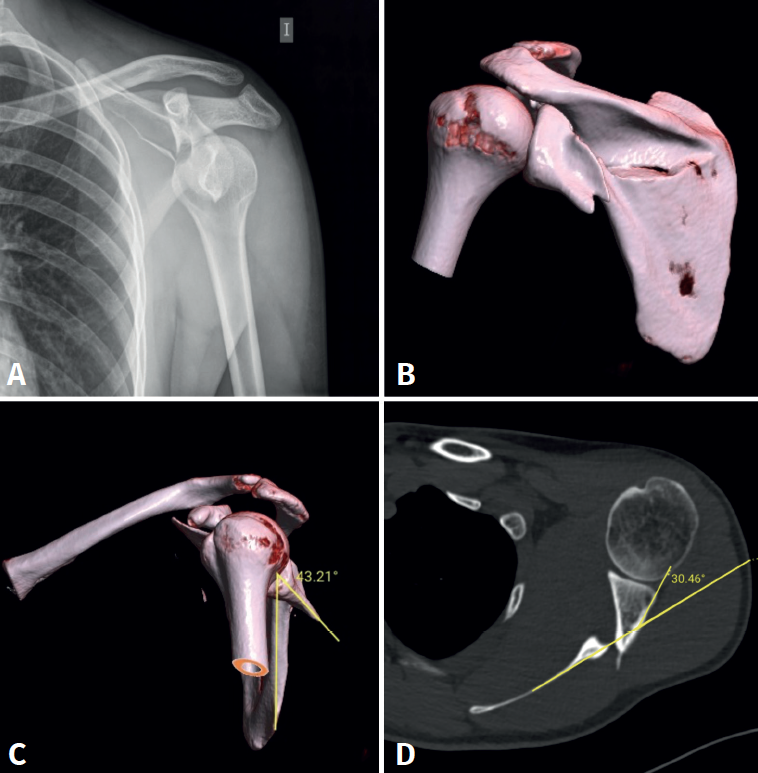

A la exploración física el paciente presenta un hematoma en la zona escapular izquierda con impotencia funcional para la movilización tanto activa como pasiva de la extremidad superior izquierda. Posteriormente, se completa el estudio de la lesión con radiografías simples y TC (Figura 1) que evidencian una fractura del cuello anatómico de la glenoides con presencia de un trazo horizontal en el cuerpo de la escápula y sin afectación intraarticular. El fragmento glenoideo presenta una rotación de 43° con una inclinación anterior de 30°; en cambio, el trazo a nivel del cuerpo de la escápula conserva una correcta alineación a pesar de su ligera conminución.